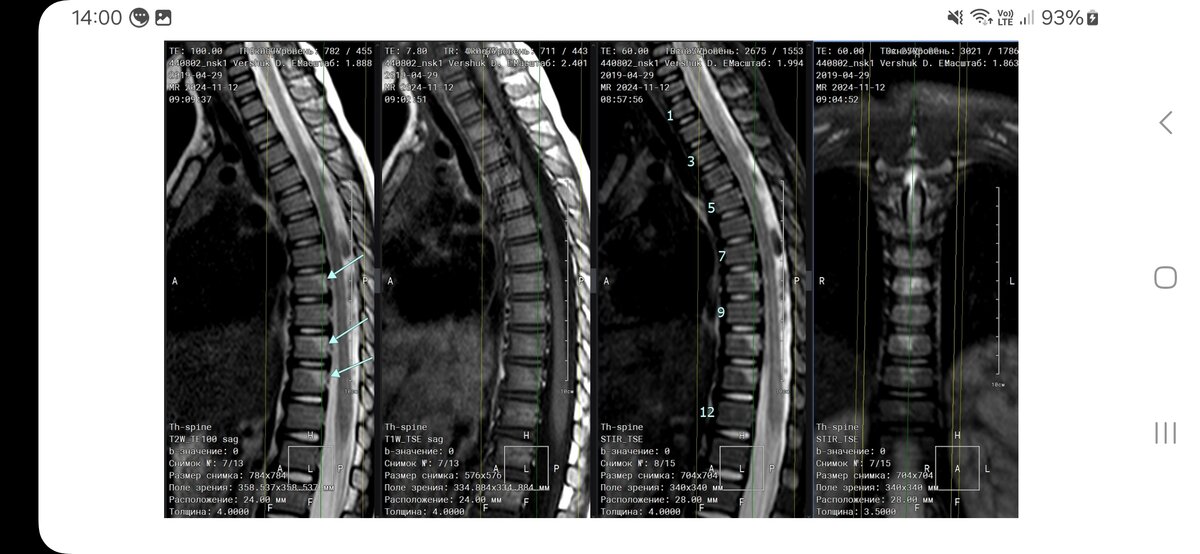

Дмитрий Олегович, добрый вечер! Подскажите, пожалуйста, ребенок приземлился на улице сплошмя на пятую точку, в итоге компрессионный перелом грудного отдела позвоночника 8, 10 и 11. Корсет, чтобы сделать, надо обязательно ложиться на красный проспект или например, к вам можно обратиться, у вас делают? И сразу лечение распишите? Как быть, подскажите пожалуйста!!! Если к вам ехать только лежа? Или можно стоя? Куда бежать?(((

Mama_35 писал(а):

Здравствуйте

Корсет нужно заказывать в корсетной мастерской, в НИИТО. Направление дам, лечение распишу. Везти ребёнка лёжа, на заднем сидении.